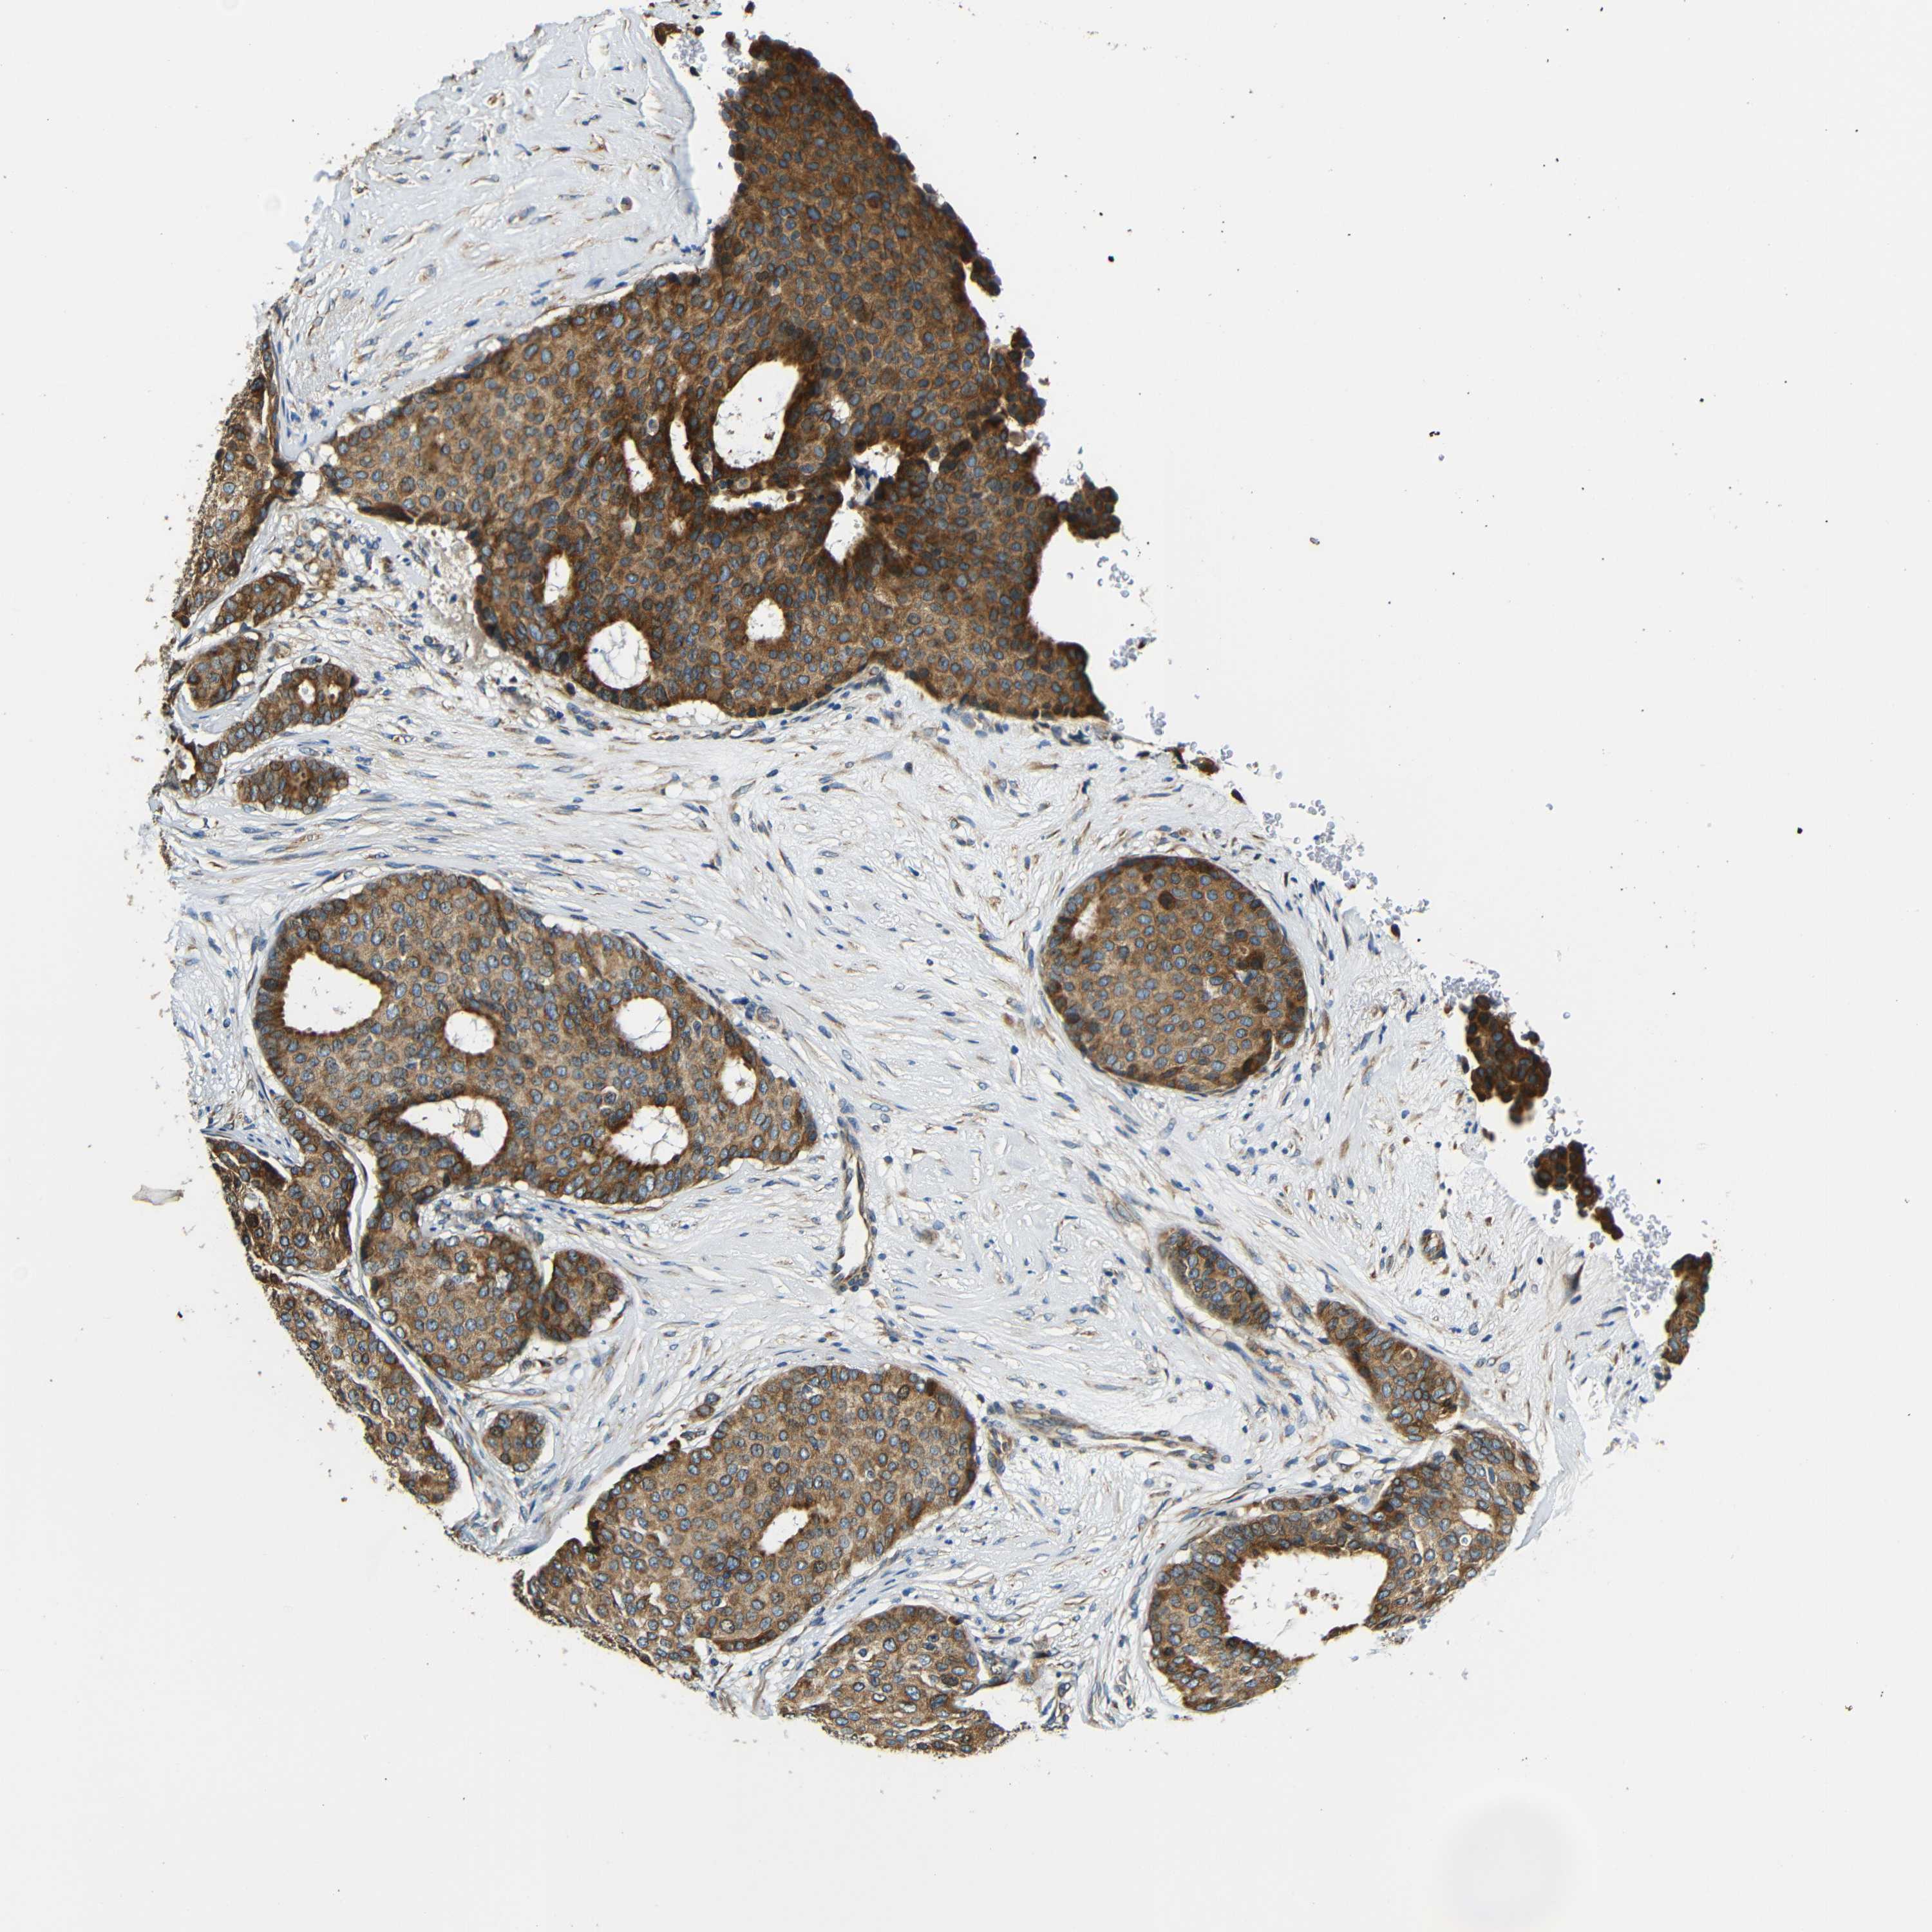

BRCA TCGA BRCA VALIDATION PROTEIN EXPRESSION